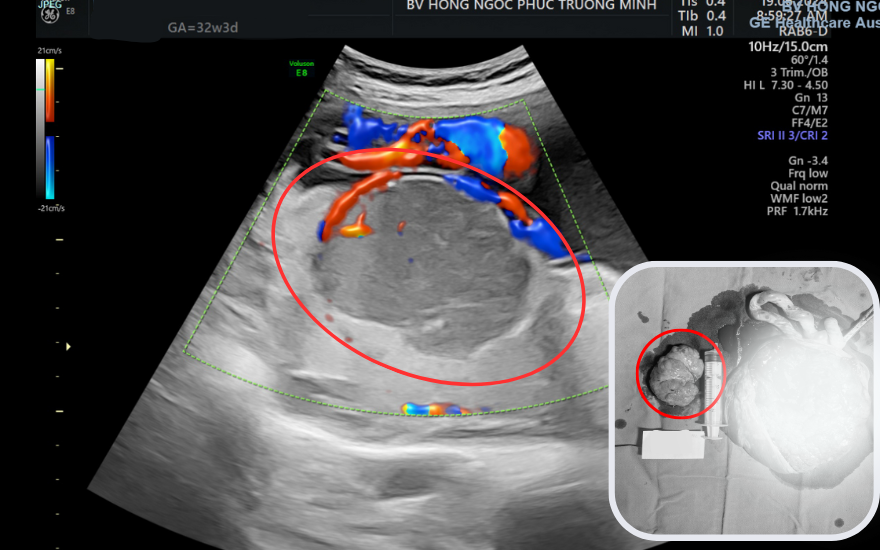

Nhờ được theo dõi sát sao và thực hiện chế độ sinh hoạt - ăn uống khoa học, đến tuần thứ 37, chị O chuyển dạ sinh thường, em bé nặng 2,9kg. Khối u được lấy ra cùng bánh nhau có kích thước 6x10cm, sinh thiết cho kết quả lành tính.

Hình ảnh siêu âm và thực tế của khối u máu bánh nhau kích thước 6x10cm